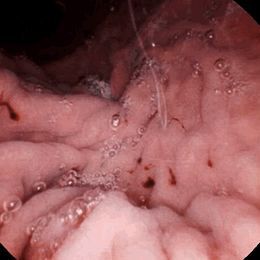

慢性胃炎的診斷主要靠胃鏡檢查,分為慢性淺表性胃炎和慢性萎縮性胃炎兩種。淺表性胃炎多發(fā)生于青壯年,胃鏡下顯示胃黏膜充血、水腫或淺表性糜爛。主要癥狀為食欲減退、上腹部脹滿不適伴疼痛等,嚴重的可引起胃出血。也可以沒有明顯的癥狀,胃酸可高、可低,也可正常。慢性萎縮性胃炎多發(fā)生于中年以后,主要表現(xiàn)為食欲不振、腹脹隱痛、噯氣、惡心嘔吐、乏力、營養(yǎng)不良和貧血,胃酸大多減少或缺乏。在慢性胃炎中萎縮性胃炎約占10%~20%。對于萎縮性胃炎的診斷,用X線拍片是很難發(fā)現(xiàn)的,必須在胃鏡下取活組織檢查,在顯微鏡下觀察活檢材料,有腺體萎縮時才能確診。一般認為,重度慢性胃炎的癌變發(fā)生率約為3%~5%。

慢性胃炎的診斷主要靠胃鏡檢查,分為慢性淺表性胃炎和慢性萎縮性胃炎兩種。

淺表性胃炎多發(fā)生于青壯年,胃鏡下顯示胃黏膜充血、水腫或淺表性糜爛。主要癥狀為食欲減退、上腹部脹滿不適伴疼痛等,嚴重的可引起胃出血。